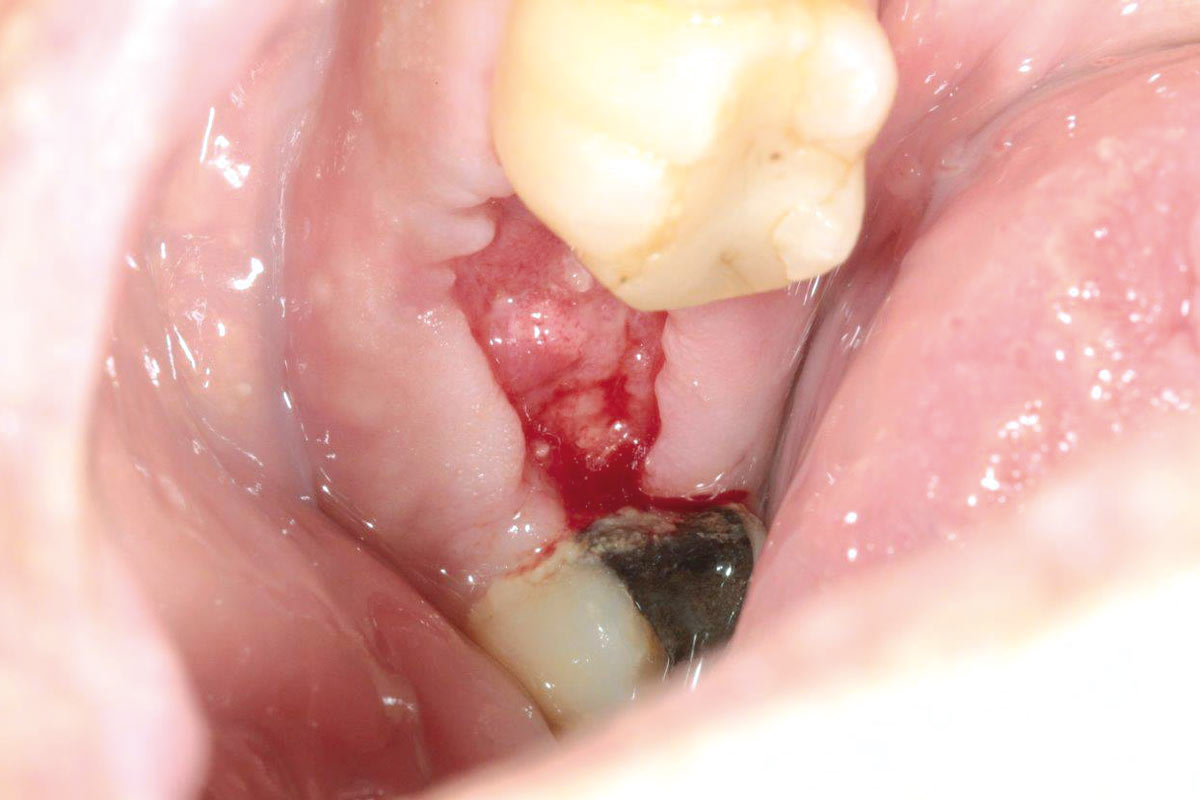

botiss cerabone® & collagen fleece for immediate implantation - Clinical case by Dr. D. Jelušić

Clinical situation before extraction and implantation